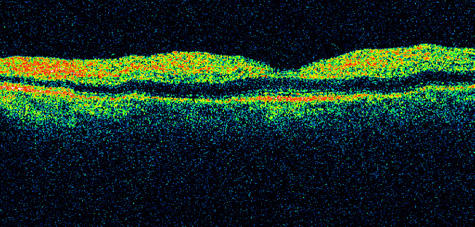

Fig. 1. A: Acute central retinal artery obstruction with a cherry-red spot. B and C: Intravenous fluorescein angiography. There is a delay of dye appearance in the central retinal artery, and when it does appear, it does not fill the arteries completely. D: Ocular coherence tomography (OCT) at the time of occlusion showing the increase in retinal thickness and reflectivity of the inner layers of the retina. E: Seven months later there is significant optic atrophy(G), and the OCT (F) shown now has marked thinning of the retina.

Optic coherence tomography (OCT) of an acute central retinal artery occlusion shows a slight increase in the thickening of the retina and reflectivity of the inner layers of the retina that correspond to the opacity seen clinically (Fig. 1).409 With time, the disc becomes atrophic and the retina thinner.